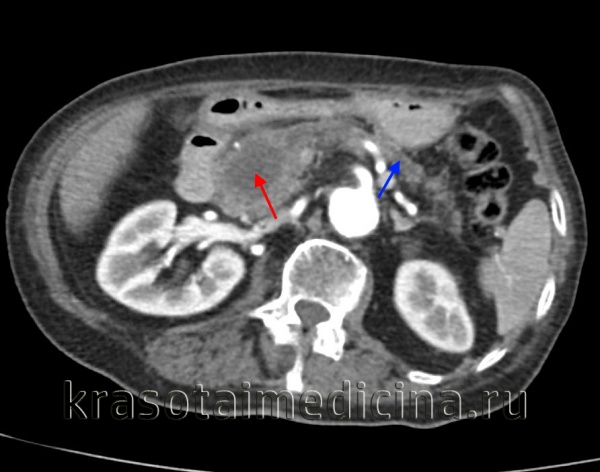

КТ ОБП/ЗП. Гиподенсная опухоль в головке поджелудочной железы (красная стрелка) на фоне расширения главного панкреатического протока и атрофии дистальных отделов железы (синяя стрелка).